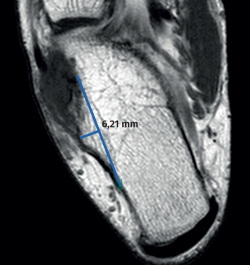

rpt.3702.fs2302004-figura3.png

Figura 3. Corte axial del calcáneo en secuencia T1 de resonancia magnética donde se muestra la medición de la altura del tubérculo peroneal.

En nuestro caso, la morfología presente fue un tipo doble convexo que, como se mencionó anteriormente, estaría presente en solo el 24% de la población y la altura fue de 6,2 mm, lo que confirma la presencia de una hipertrofia de esta estructura. La medición de la altura fue realizada en el corte axial de resonancia en la secuencia T1, desde el vértice del tubérculo hasta una línea trazada en la cortical lateral del calcáneo, según lo descrito por Saupe et al.(13).